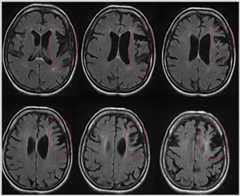

Case 5-1

A 54-year-old man presented to the psychiatric emergency department for bizarre behavior, claiming he had won the lottery. The family reported that 6 years prior to presentation he became less organized managing his finances. The family discovered 3 years ago that bills, including the mortgage, were going unpaid, and he had accumulated significant credit card debt. His affect became flat and his family reported that it was “hard to get a reaction out of him.” He began to cook in an impulsive way, turning the burners on maximum for everything. The patient had lost his job for inappropriate borrowing of money from clients 1 year prior to presentation. He began buying multiple lottery tickets each week, and despite financial difficulties, he purchased a luxury motorcycle. He began wearing the same clothing multiple days in a row and required encouragement to shower. He lost interest in his hobbies and spent increasing amounts of time “staring” at the television. Family history was negative for any neurodegenerative diseases, although his father died in his forties of a myocardial infarction, and his mother died in her early sixties of cancer. On examination, the patient was mildly unkempt, with a flat affect, and appeared apathetic. His speech was fluent with preserved naming, repetition, and comprehension. Cranial nerves were intact, including normal saccades. There was no evidence of bradykinesia. Sensory and motor examinations were normal. He had mild difficulty performing the Luria hand sequence (a three-step hand movement sequence of fist-side-flat) on the left compared to the right. Snout and grasp reflexes were absent (normal). On cognitive testing, he scored 26 out of 30 on the Mini-Mental State Examination (MMSE) and 14 out of 30 on the Montreal Cognitive Assessment (MoCA), losing points for attention, concentration, working memory items, and Trail Making B test sample. Semantic and phonemic fluency were both moderately impaired. MRI imaging demonstrated bifrontal and temporal atrophy (Figure 5-1). Subsequent genetic testing forC9ORF72,GRN, andMAPT did not reveal any pathogenic mutations. A diagnosis of probable behavioral variant of frontotemporal dementia (FTD) was made. He was advised to stop driving and was reported to the Department of Transportation. Family were referred to a social worker and an FTD caregiver support group. Citalopram 20 mg/d was started with modest improvement of the obsessive behaviors.

Figure 5-1.

T2-weighted axial MRI shows bifrontal and temporal atrophy in the patient inCase 5-1 with sporadic behavioral variant of frontotemporal dementia.